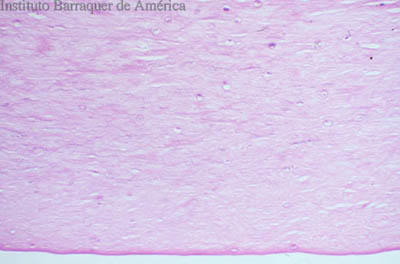

Tejido corneal Procesado

H&E

PAS

CW

PAS